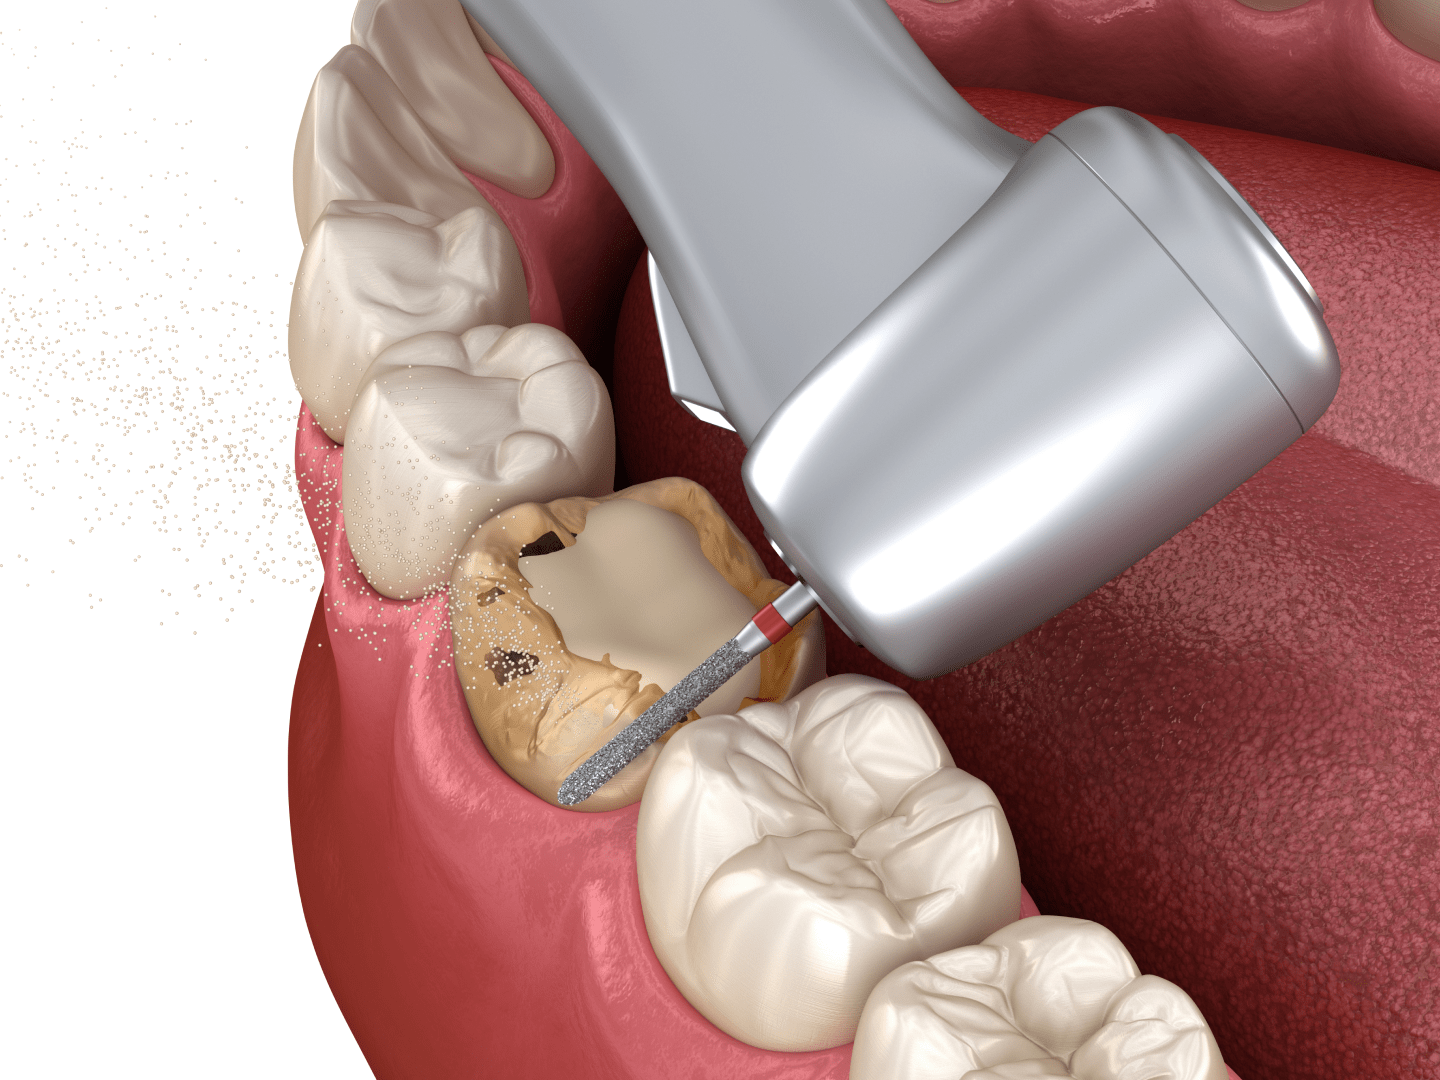

- Перед встановленням коронки іноді необхідно провести депульпування зуба, оскільки під час підготовки знімається значний об’єм його тканин.

Як відбувається протезування металокерамікою

Металокерамічні коронки в клініці ЦІС зазвичай встановлюються за 2–3 візити до стоматолога. Процедура складається з декількох етапів.